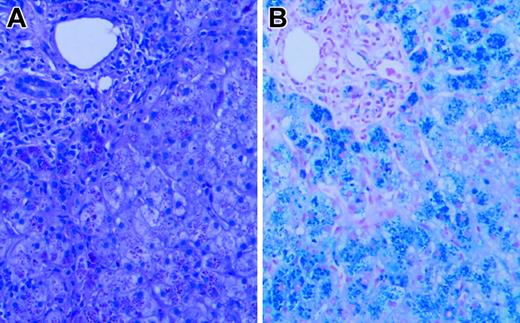

Liver biopsy revealed grade 4 hepatic parenchymal cell-stainable iron (Figure 1), portal and lobular inflammation (grade 3/4), and architectural distortion with portal-septal fibrosis (stage 3). Liver iron content by atomic absorption spectrophotometry was markedly elevated at 1500 μg iron/100 mg dry weight (normal, 1-17 μg iron/100 mg dry weight). Sequence analysis of HFE and HAMP revealed no mutations. Serum gonadotrophin analysis and intravenous glucose tolerance/insulin secretion test confirmed the presence of hypogonadotropic hypogonadism and diabetes, but endocrine function was otherwise normal.

Liver biopsy. Hematoxylin and eosin (A) and Prussian blue iron (B) stains of the patient's liver biopsy specimen at the time of diagnosis, demonstrating heavy (4+) hepatocellular iron deposition. Slides were viewed with a Nikon Eclipse E600 microscope equipped with a 40×/0.75 objective lens (Nikon, Melville, NY). An RT Slider SPOT 2.3.1. camera and SPOT advanced software (v.3.5.9; Diagnostic Instruments, Sterling Heights, MI) were used to capture images.